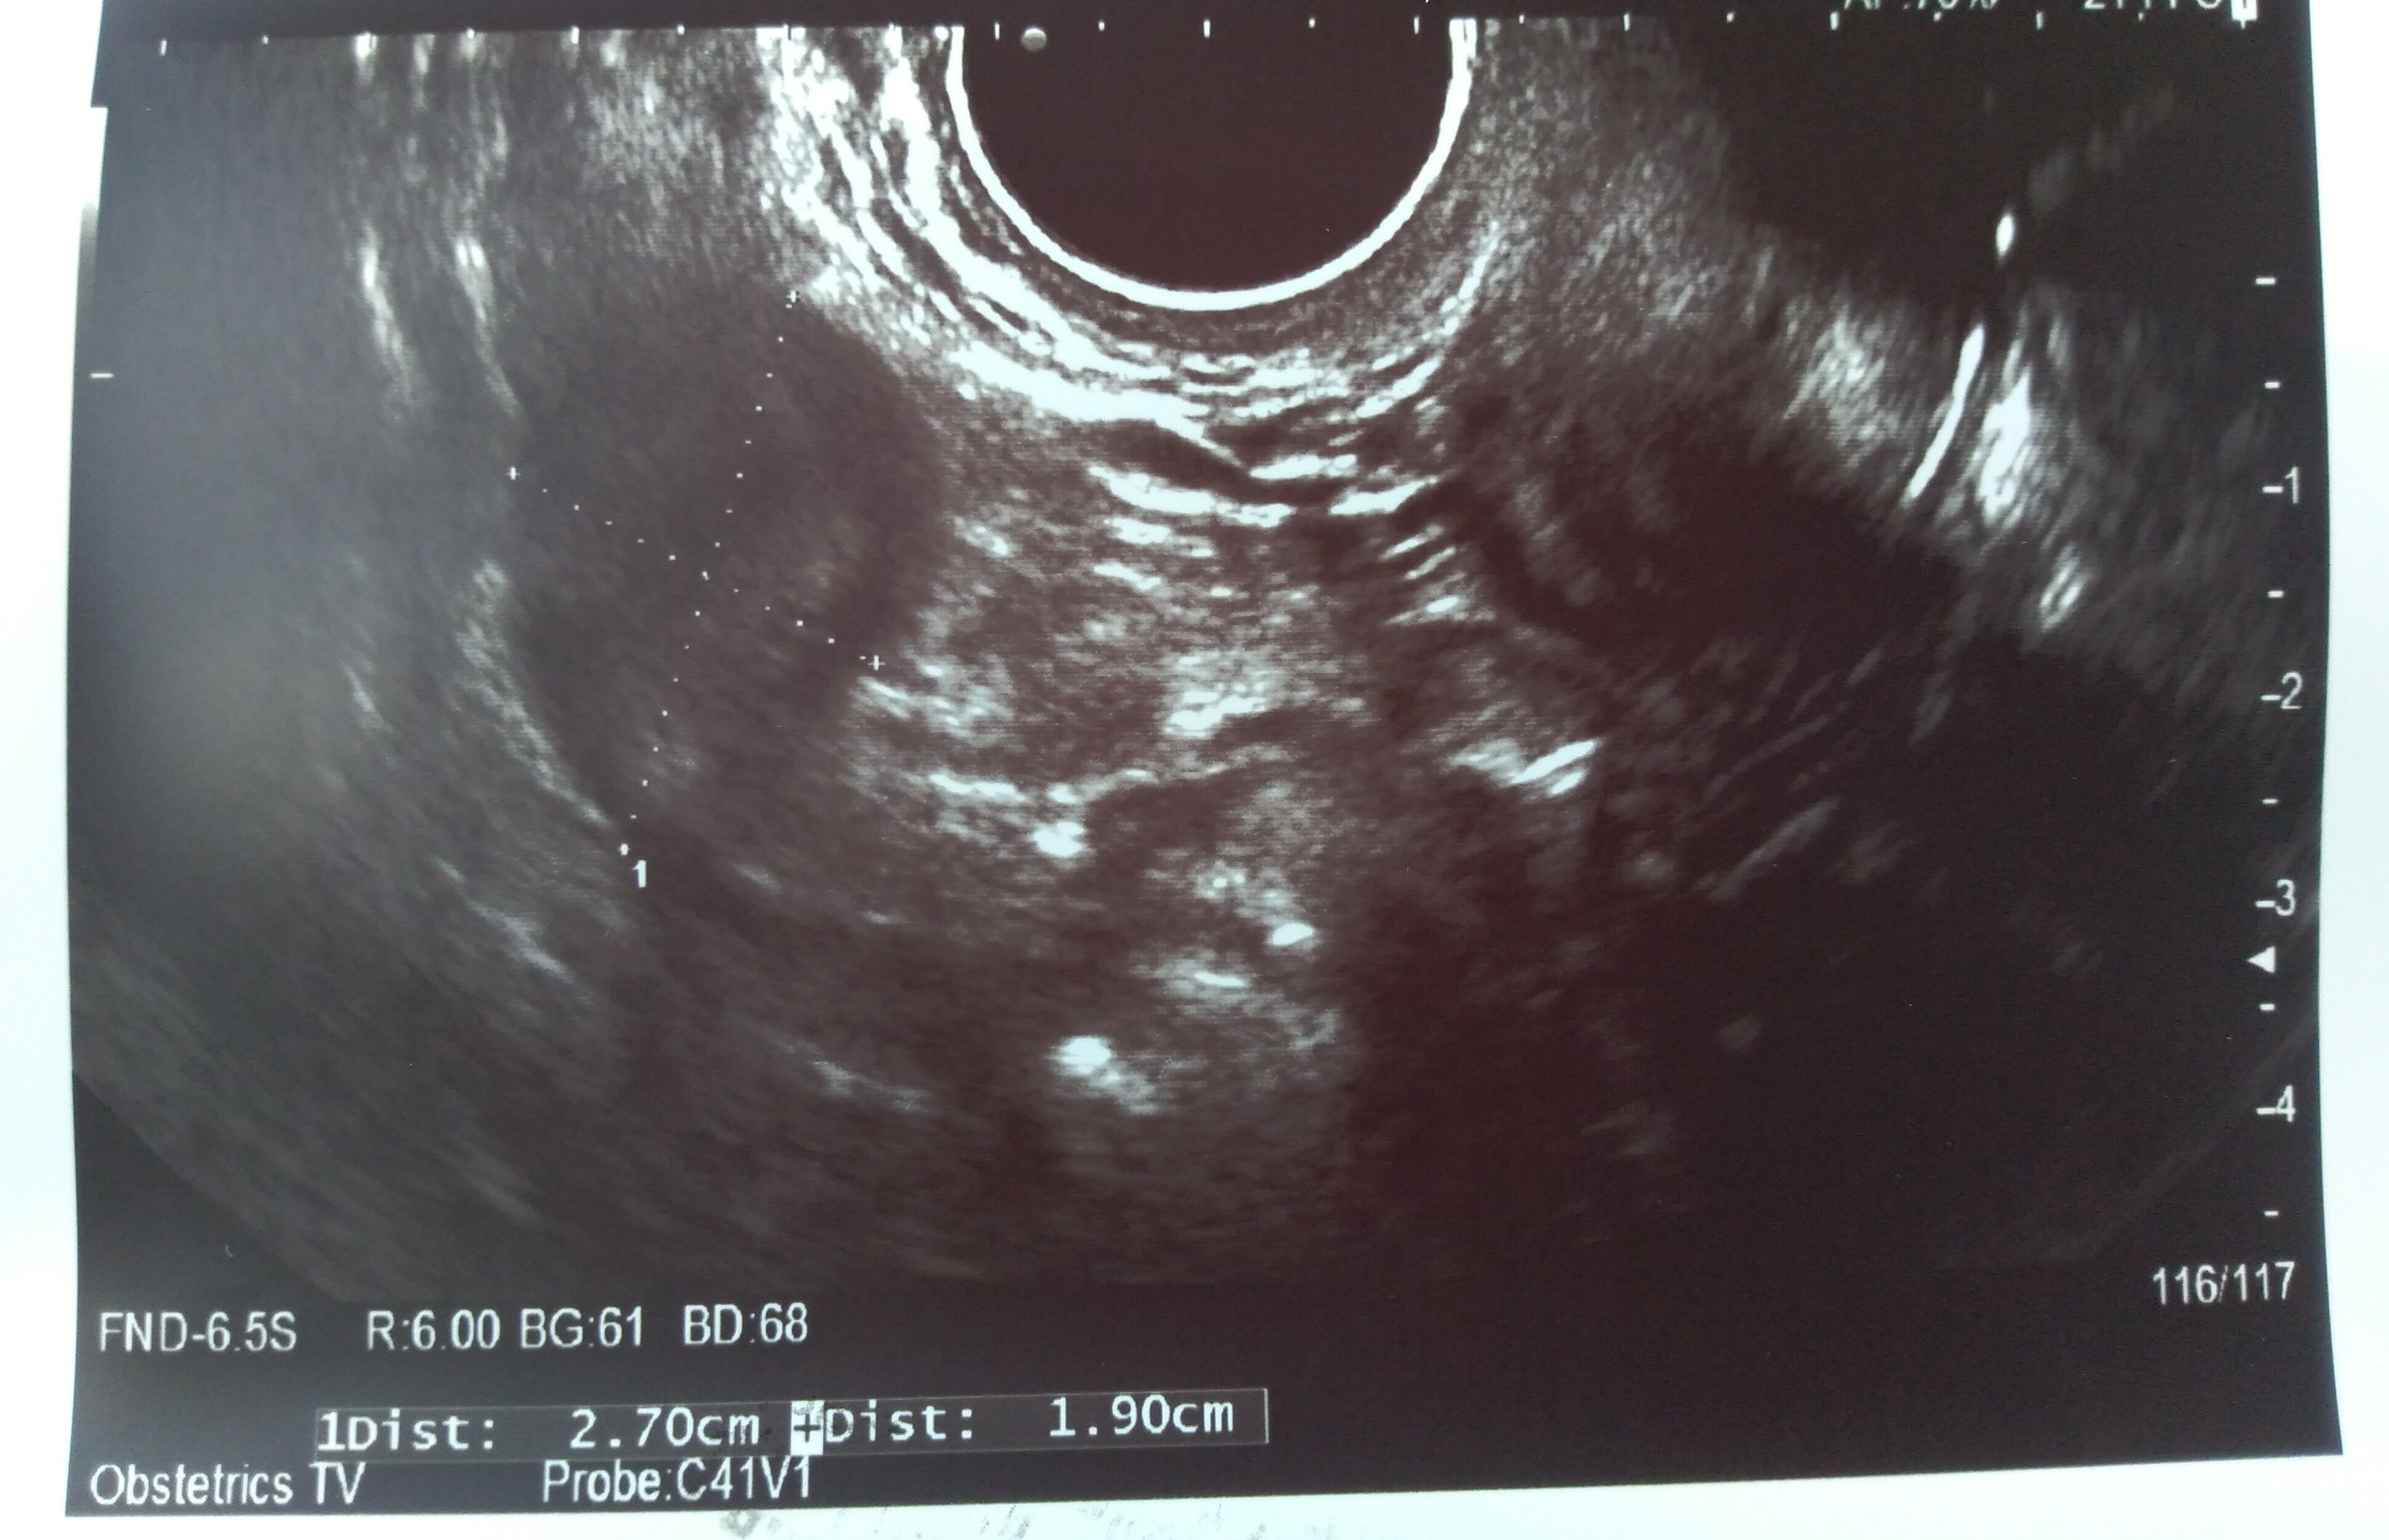

Hej dziewczyny, byłam na usg. Nie wiem co o tym myślećpowiedziała, że pęcherzyk ciążowy jest za mały na swój wiek. Ma 1,21 cm. Według aplikacji dziś 6+1

jest zarodek 2,9 mm. Serduszko bije 111/min. Nie puściła mi do słuchania tylko liczyła, widziałam jak faluje.

Jednak ciąża jakby jest młodsza o 2 tyg - usg pokazuje 4+2

Dodatkowo mam krwiaka większego dwa razy od pęcherzyka ciążowego - ma 8 na 5 i obok jakieś jeszcze mniejsze...

Różowa strzałka wskazująca to krwiak. Te duże coś na 5 cm to nawet już nie wiem z tego wszystkiego co to było